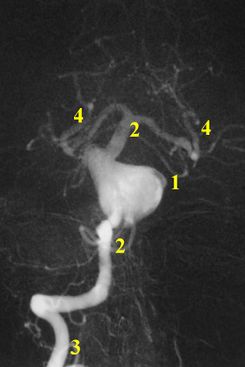

نزف تحت العنكبوتية Subarachnoid hemorrhage (SAH)، أو subarachnoid haemorrhage، هو نزيف داخل الحيز تحت العنكبوتية subarachnoid space المحيط بالمخ، وهي المنطقة بين الغشاء العنكبوني arachnoid membrane والأم الحنون pia mater. فيه يحدث النزف ضمن الطبقة السحائية العنكبوتية. وأكثر الأسباب شيوعاً هو رضوض الدماغ، أما حالات النزف غير الرَّضِّيّ فتنتج عادة من انفجار أم دم aneurysm (وهي توسع كيسي غير طبيعي في شريان أو أكثر). ومن الأسباب الأخرى التشوهات الشريانية الوريدية، والتهاب الأوعية، وتسلخ الشرايين، واعتلالات التخثر، وخثار الجيوب الوريدية، وفقر الدم المنجلي، وتمزق شريان سطحي صغير. ويبقى السبب مجهولاً في نحو 14ـ22% من الحالات. وفيما يأتي نبذة عن النزف تحت العنكبوتية الناتج من أمهات الدم لكونه الأهم بينها.[1]

Spontaneous SAH is most often due to rupture of cerebral aneurysms (85%), or weaknesses in the wall of the arteries of the brain that become enlarged. In 15-20% of cases of spontaneous SAH, no aneurysm is detected from the first angiogram.[2]